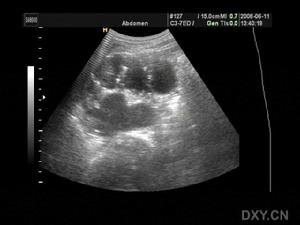

糖尿病性腎病變一般資料

1996年~1999年一共收集符合DM性腎病變患者108例,隨機分為黃芪注射液治療組72例和補中益氣湯對照組36例。其中男性63例,女性45例,年齡38~82歲,平均57.2±11.4歲,病程3~32年,平均8.31±4.15年,症狀、體徵為蛋白尿(100%)、高血壓(89%)、雙下肢浮腫(82%)、氮質血症(Scr178~442umol/L)47例,尿毒症(Scr>442umol/L)9例,頭暈昏沉(100%)、神疲倦怠(99%)、心悸氣短(86%)、腹脹納呆(42%)、腰膝酸軟(62%)、舌苔滑膩(59%)、脈沉(81%)、弦(52%)、滑(87%)、細(50%),經χ2檢驗,兩組間性別、年齡、病程、體徵、症狀等均無顯著性差異(P>0.05)。